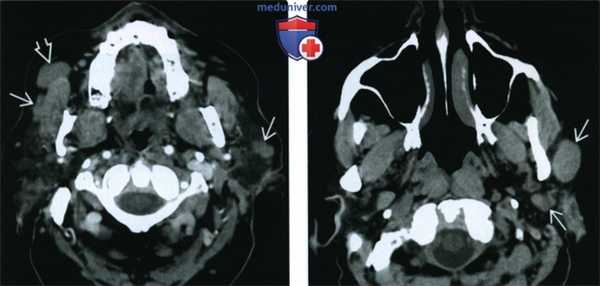

(Слева) КТ с КУ. Визуализируются множественные двусторонние округлые опухоли Вартина, плохо накапливающие контраст. Обратите внимание, что справа опухоль захватывает добавочную долю околоушной железы.

(Справа) КТ без КУ, аксиальная проекция. Наблюдаются множественные округлые опухоли Вартина. Контуры опухолей четкие, размеры варьируют. В 20% случаев заболевание носит множественную форму. Новообразования могут возникать как в одной, так и в обеих железах.в) Дифференциальная диагностика опухоли Вартина:

(Слева) На аксиальной КТ с КУ в околоушных железах определяются множественные двухсторонние опухоли Уортина овоидной формы, плохо накапливающие контраст. Обратите особенное внимание на опухоль в добавочной доле околоушной железы.

(Справа) На аксиальной КТ без КУ в левой околоушной железе визуализируются множественные овоидные, хорошо отграниченные опухоли Уортина различного размера. У 20% пациентов опухоли Уортина множественные (множественные очаги в одной железе или в обеих).в) Дифференциальная диагностика опухоли Уортина: